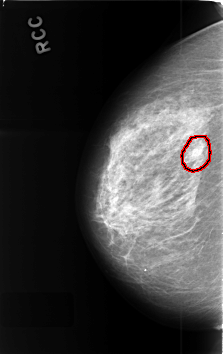

C_0420_1.RIGHT_CC

RIGHT_CC LINES 4592 PIXELS_PER_LINE 2888 BITS_PER_PIXEL 12 RESOLUTION 50 OVERLAY

FILE: C_0420_1.RIGHT_CC.OVERLAY

TOTAL_ABNORMALITIES 1

ABNORMALITY 1

LESION_TYPE MASS SHAPE OVAL MARGINS CIRCUMSCRIBED

ASSESSMENT 3

SUBTLETY 3

PATHOLOGY BENIGN_WITHOUT_CALLBACK

TOTAL_OUTLINES 1

BOUNDARY